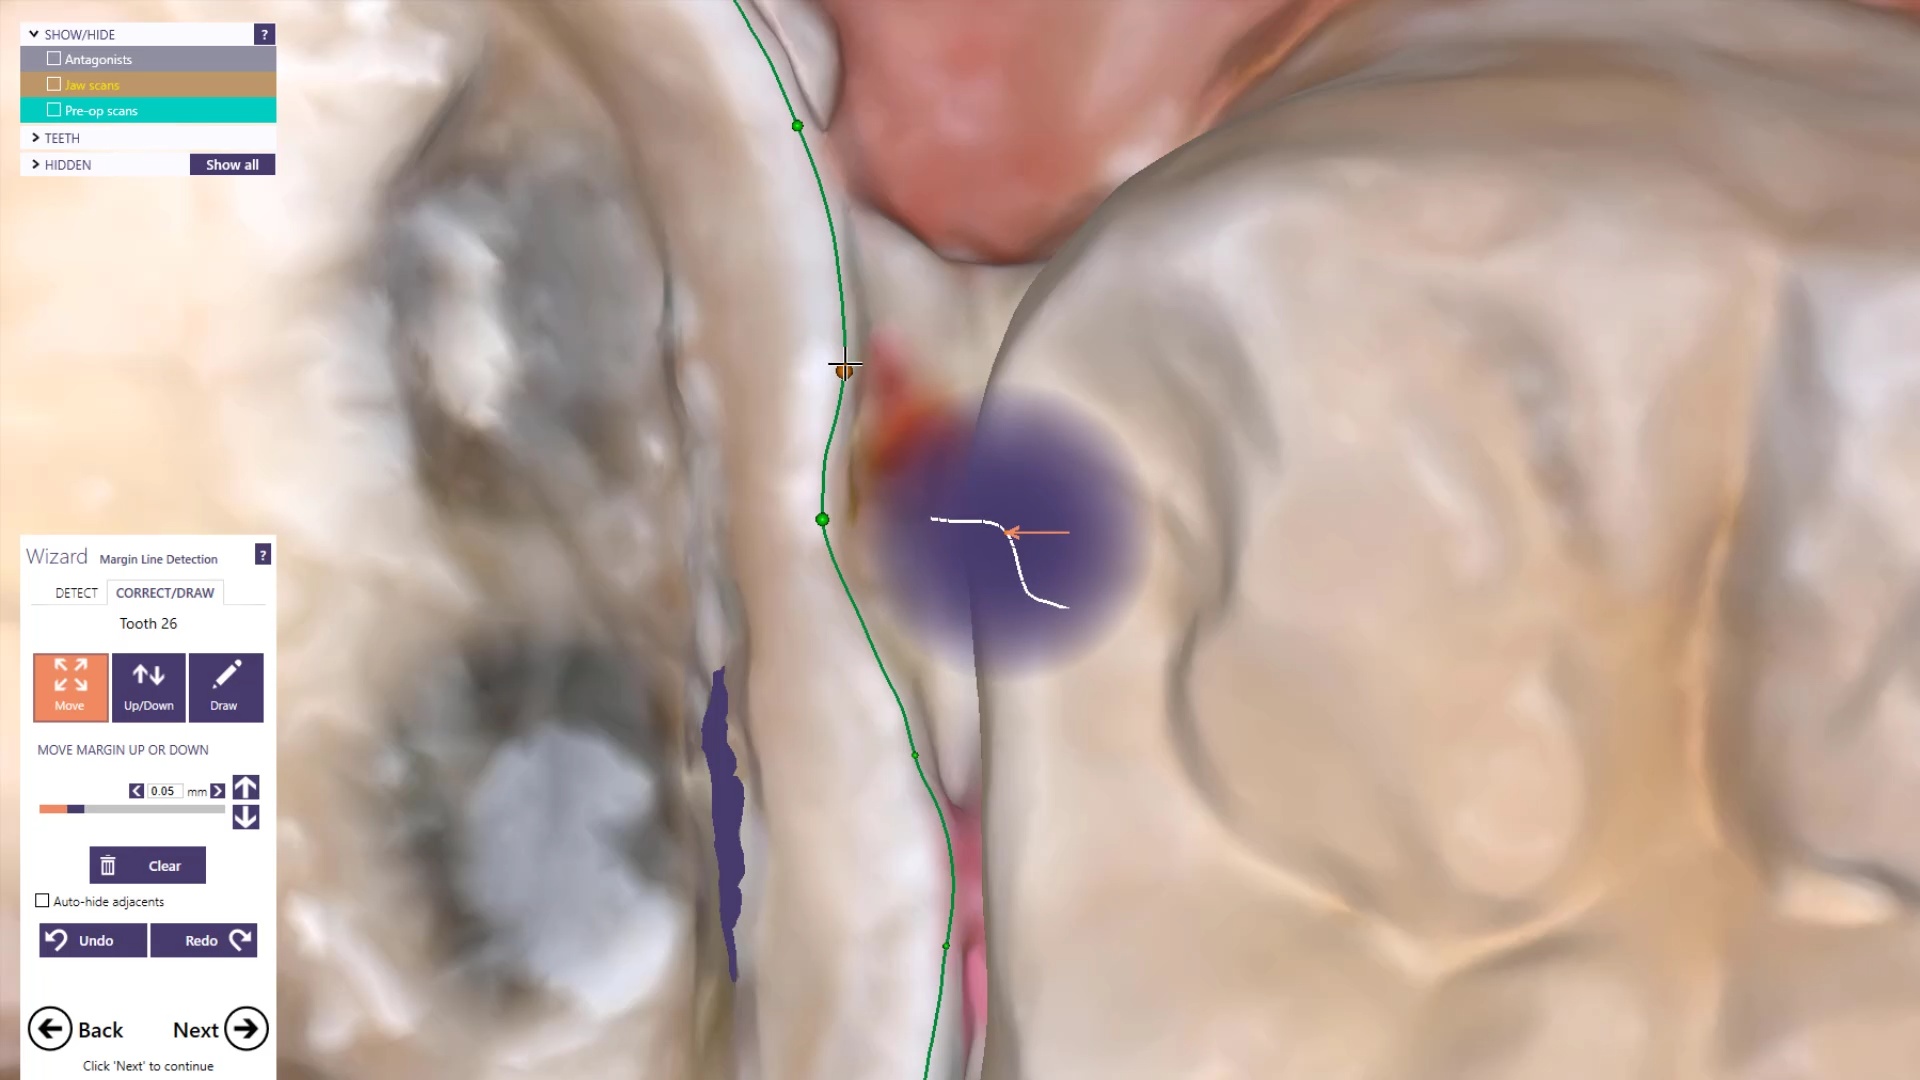

Once you have adequate clearance, retraction, and hemostatis, you can readily image and find your margins in the CAD software